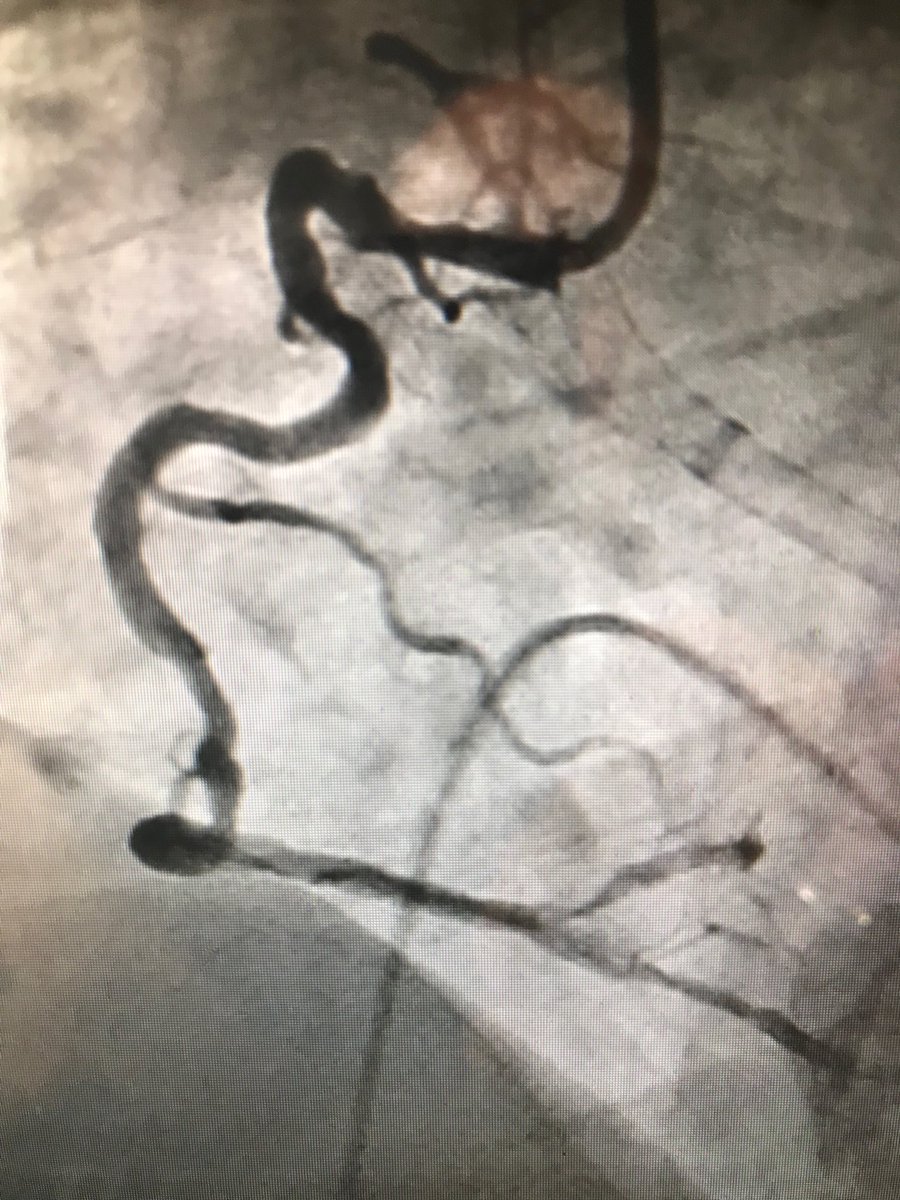

38m cp 30 hrs nstemi #RadialFirst opened LAD, brought back 2 weeks 7f guide #safefemoral #protectedpci #impella #ivus 4.5 DES in LAD>LM. Pot 5.0 #preclose home next day EF now 50

istentem's tweet image. 38m cp 30 hrs nstemi #RadialFirst opened LAD, brought back 2 weeks 7f guide #safefemoral #protectedpci #impella #ivus 4.5 DES in LAD>LM. Pot 5.0 #preclose home next day EF now 50